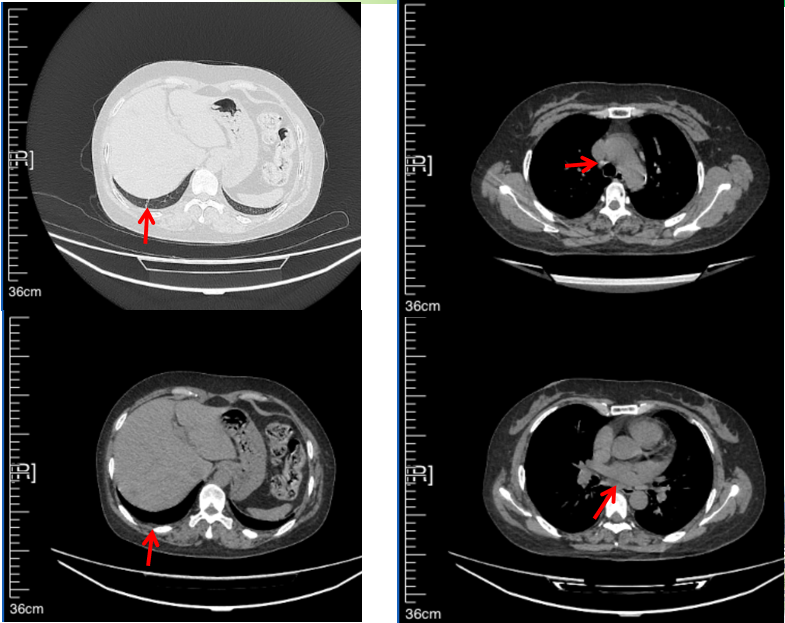

治疗经过:2023年3月27日始行恩沙替尼靶向治疗至今,最佳疗效为PR,末次评效为维持PR。期间出现轻度肝功能异常(DILI 1级),对症处理后好转。截止目前PFS为26个月。

2023年2月20日基线检查

2024年6月复查PR(最佳疗效)

2024年12月复查维持PR

2025年3月复查维持PR